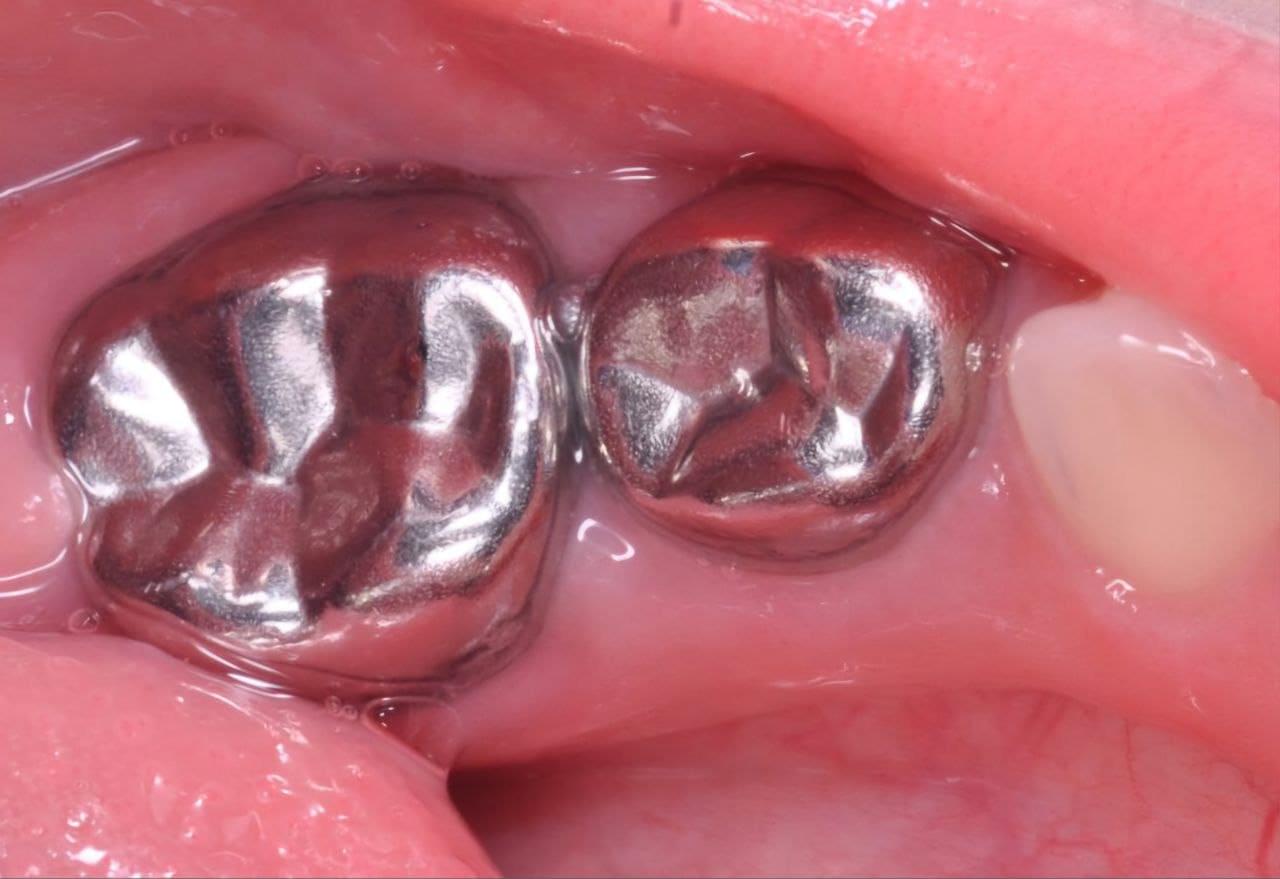

Дівчинка, 5 років. Лікування зворотнього пульпіту тимчасових зубів 85,84 та їх відновлення за допомогою стандартних металевих коронок. Лікування проводилось в умовах закису азоту кисневої седації. Період зміни зубів - 10-12 років.